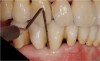

The teeth were prepared without violating the biologic width with intracrevicular preparations (Figure 3) and final impressions were made to establish master models, which were mounted using an electronic pantographic record. This record determined the condylar settings necessary to set an Arcon articulator. (There are now many articulators that are fully adjustable and easily programmable.) The master casts were made and mounted with a facebow to an Arcon articulator.

Figure 3 Tooth preparations were completed for full-coverage monolithic ceramic restorations.

Figure 3